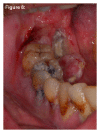

Infections are increasingly considered as potential trigger for carcinogenesis apart from risk factors like alcohol and tobacco. The discussion about human papilloma virus (HPV) in oral squamous cell carcinoma (OSCC) points at a general role of infection for the development of oral carcinomas. Furthermore, first studies describe a correlation between chronic periodontitis and OSCC, thus, characterizing chronic inflammation as being a possible trigger for OSCC. In front of this background, we present four well-documented clinical cases. All patients showed a significant anatomical relation between OSCC and clinical signs of chronic periodontitis. The interindividual differences of the clinical findings lead to different theoretical concepts: two with coincidental appearance of OSCC and chronic periodontitis and two with possible de novo development of OSCC triggered by chronic inflammation. We conclude that the activation of different inflammatory cascades by chronic periodontitis negatively affects mucosa and bone. Furthermore, the inflammatory response has the potential to activate carcinogenesis. Apart from a mere coincidental occurrence, two out of four patients give first clinical hints for a model wherein chronic periodontitis represents a potential risk factor for the development of OSCC.